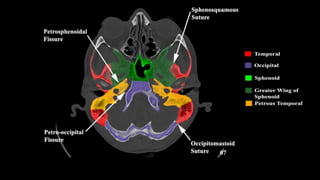

Pseudo-fractures

Extrinsic Fissures &

Sutures